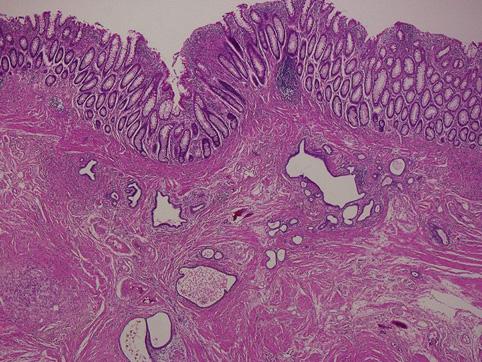

疾患(病理主体)の分類腫瘍様病変/子宮内膜症

部位(臓器別)大腸/直腸

検査方法ミクロ

病変の最大径(ミリ)40以上